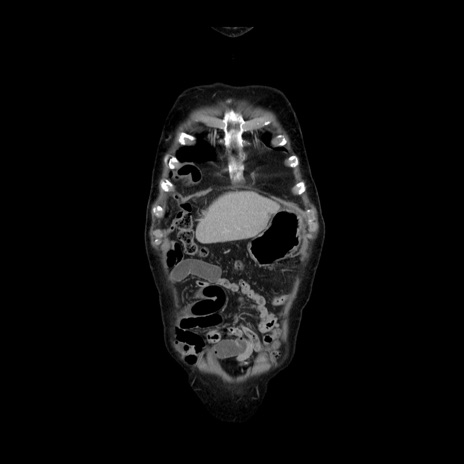

横断像

【症例】70歳代男性

【主訴】腹痛

【現病歴】肝硬変・肝細胞癌にてかかりつけの方。約9時間前に食後より腹痛出現。症状が徐々に増悪し、嘔吐出現したため来院。

【既往歴】肝硬変、肝細胞癌(RFA、TACE後)

【身体所見】意識清明、表情苦悶様、BT 36℃、BP 129/78mmHg、P 88bpm、SpO2 97%(RA)、右上腹部から心窩部にかけて圧痛あり、反跳痛なし、筋性防御あり。

【データ】WBC 5800、CRP 0.16